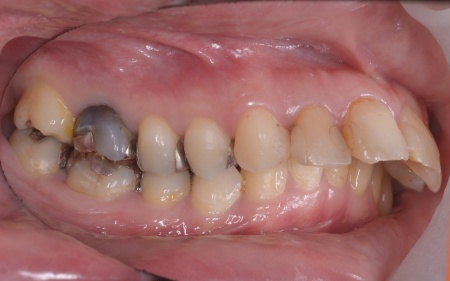

| カウンセリング | 拝見したところ、上前歯が大きく前に出ている上顎前突であり、上下の前歯が噛み合わずに口を閉じても前歯同士が接触しない「開咬(かいこう)」の状態でした。 レントゲン撮影をして詳しく調べた結果、歯の位置だけでなく、骨格的な問題があることが分かりました。 また、前歯で食べ物をうまく噛み切ることができないため、奥歯にも強い負担がかかっているだけでなく、このまま放置すると、奥歯がすり減ったり痛みが生じたりするリスクもあります。 以上のことから、噛み合わせを改善する治療が必要だと診断しました。 |

患者様の場合、骨格的な上顎前突が噛み合わせを乱している主な原因であることから、矯正治療では前歯を後方へ大きく動かすためのスペースを確保する必要があります。 そのため、今回は以下2つの方法を提案しました。 ①抜歯後、アンカースクリューを用いたワイヤー矯正 メリット:骨格的な上顎前突に対応しやすく、前歯を大きく後方へ動かすことができる ②取り外し可能な装置を使用するマウスピース矯正 メリット:装置が透明で目立ちにくく、取り外しができる 以上のメリットとデメリットを丁寧にお伝えしたところ、患者様は①のアンカースクリューを用いたワイヤー矯正を選択されました。 まず、上顎の左右奥歯を抜き、前歯を後方に動かすためのスペースを確保します。 治療の結果、前歯が正しく噛み合うようになり、横顔のバランスも整いました。 矯正治療終了後は、歯が元の場所に戻らないよう上下前歯に保定装置(リテーナー)を装着し、治療を終了しています。 |